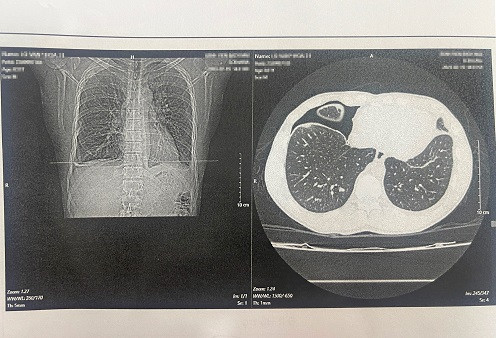

| Hình ảnh phim chụp trên bệnh nhân nhiễm sán lá phổi. Ảnh: Bệnh viện cung cấp |

Trung tâm Bệnh nhiệt đới, Bệnh viện Bạch Mai (Hà Nội) tiếp nhận một bệnh nhân nam (SN 1992, người dân tộc Thái, thường trú ở Điện Biên) trong tình trạng tràn dịch, tràn khí màng phổi. Sau khi được bác sĩ chỉ định xét nghiệm ký sinh trùng thì phát hiện dương tính với Paragonimus (sán lá phổi).